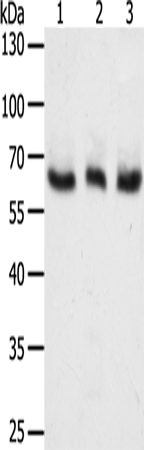

分类: 科研抗体货号: P07697别名:应用: WB,IHC反应种属: Human, Mouse